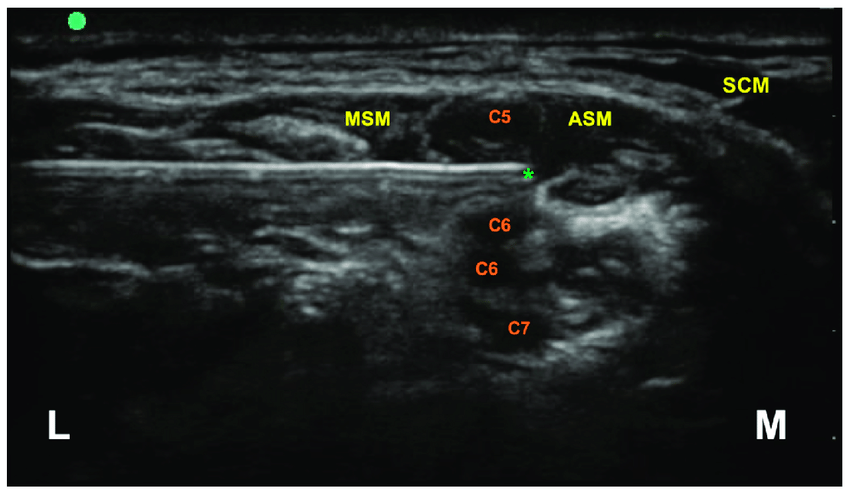

So when you are looking at 3-5 black circles in the interscalene groove, how do you differentiate which ones are C5, C6, C7 vs. multiples coming off the same root? For example how do we know in the picture below that we are not looking at C5, C6, C6, C7 (or any other anatomical variant).

So when you are looking at 3-5 black circles in the interscalene groove, how do you differentiate which ones are C5, C6, C7 vs. multiples coming off the same root? For example how do we know in the picture below that we are not looking at C5, C6, C6, C7 (or any other anatomical variant).